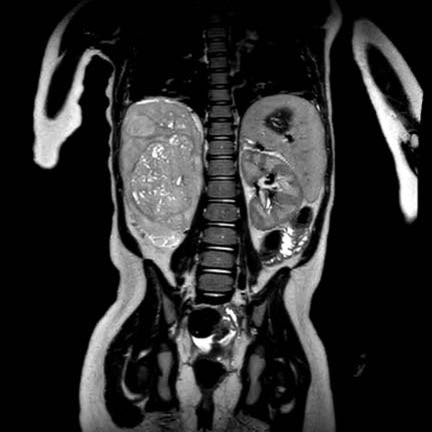

Video này của bé gái ba tuổi có khối lớn ở hố thắt lưng phải.

Siêu âm với đầu dò tần số cao cho thấy khối u xuất phát từ thận phải.

Phần đài bể thận còn lại bị giãn, đây là trường hợp thường gặp.

Hình ảnh MRI cho thấy mức độ lan rộng của khối u.

Lưu ý huyết khối u trong tĩnh mạch chủ dưới.